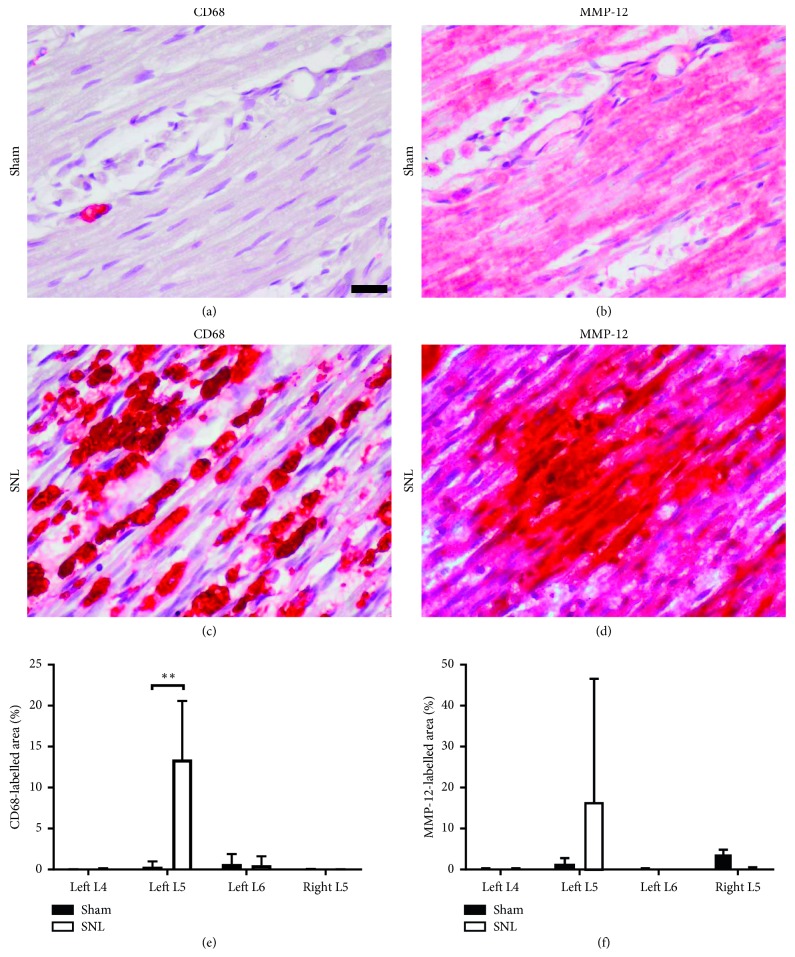

3.2. Macrophage Infiltration and MMP-12 Upregulation Observed in Ligated Spinal Nerves

One-week postoperative immunostaining for CD68 and MMP-12 showed greater staining in ligated left L5 spinal nerves (CCD68 13.4 ± 7.15%; MMP-12 23.6 ± 18.4%), compared to the left L5 spinal nerves in sham-operated rats (CD68 0.335 ± 0.656%; MMP-12 9.91 ± 9.30%). In SNL rats, CD68 and MMP-12 staining in the left L4, left L6, and right L5 spinal nerves were lower than the left L5 spinal nerve (Figure 2). MMP-12 activity analysis (Figure 3) at 1 week after SNL further confirmed ligation induced significant MMP-12 upregulation in left L5 spinal nerves (0.455 ± 0.253), compared to sham surgery (0.106 ± 0.0900). Moreover, MMP-12 expression remained elevated in left L5 spinal nerves 2 weeks after SNL (0.510 ± 0.374). Hence, the MMP-12-targeted probe was administered 2 weeks after SNL or sham surgery, to ensure animals were fit for intrathecal injection. While sham surgery also induced detectable MMP-12 levels, it is lower than the corresponding spinal nerves in SNL rats. MMP-12 upregulation was observed in spinal nerves contralateral and ipsilateral to the ligated left L5 spinal nerve too. This may be due to local inflammation in response to surgical insult. Nevertheless, MMP-12 levels of nonligated nerves in SNL rats were still lower than ligated nerves. Furthermore, MMP-12 levels in nonligated nerves reduced between 1 and 2 weeks after SNL but increased in ligated nerves, suggesting local inflammation subsidence over time. Taken together, the results suggest that macrophage infiltration occurred primarily at the site of ligation, leading to increased MMP-12 secretion at the pain-generating site [21].

Figure 2.

Macrophage infiltration and MMP-12 upregulation occurred in injured nerves. (a–d) Representative images of immunohistochemistry staining on consecutive sections for macrophage marker CD68 and MMP-12, in the left L5 spinal nerves distal to the DRG, 1 week after SNL or sham surgery (CD68 or MMP-12: red, nuclei: purple, scale bar = 20 μm). (e) CD68- and (f) MMP-12-labelled areas were quantified for SNL and sham rats' spinal nerves (n=5 per group). Statistically significant difference in the left L5 spinal nerve CD68-labelled area was determined by Mann–Whitney U test (∗∗p < 0.01).